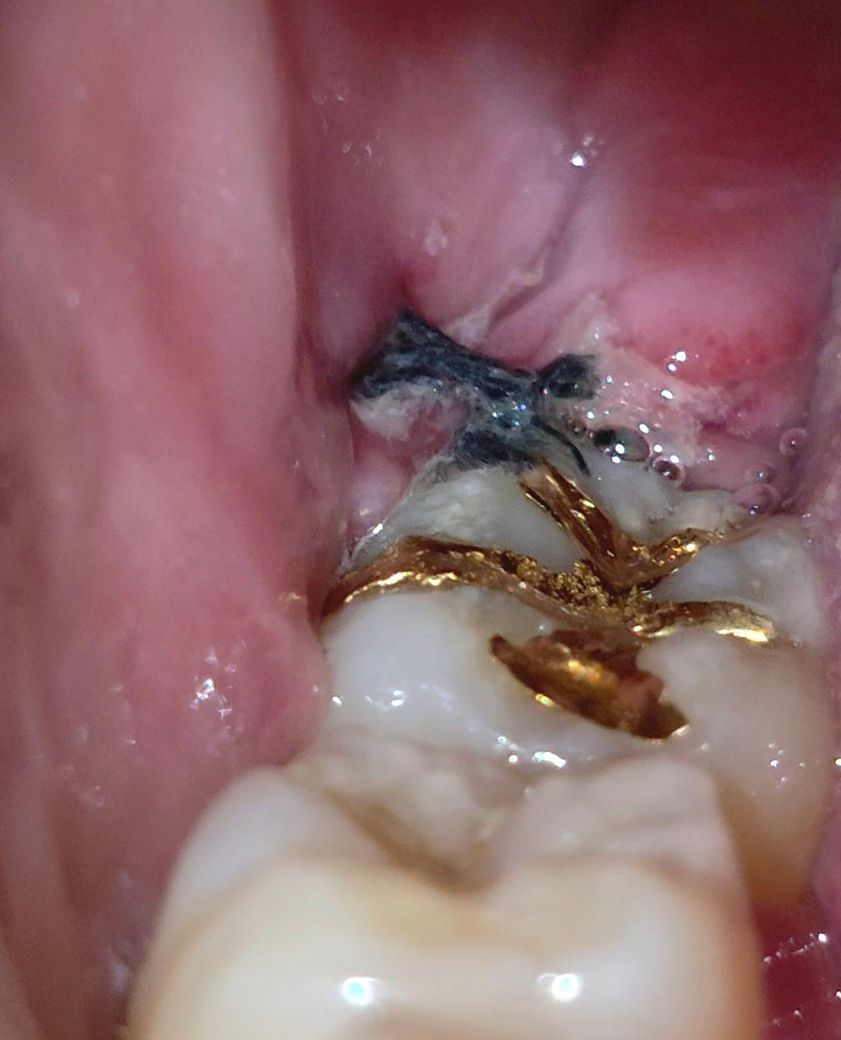

사랑니 발치 후 치유과정 (사진 있음)

8월 13일(수요일) 09시에 대학병원에서 우측하악(48번)수평매복사랑니 발치하고, 8월 17일(일요일) 09시 사진인데(4일차), 정상적으로 치유되고 있는 과정인지 사진상으로도 확인가능할까요? 감사합니다.

• 1번 째 사진

사지상으로 보면 잘 아물고 잇는거 같습니다. 잇몸이 치유되면서 생기는 자연스러운 현상이니 자극만 가지 않도록 해주세요.

매복된 사랑니를 발치하고 나면 잇몸 손상이 크기 때문에 통증이 있거나 불편감이 있을 수 있습니다. 사진으로 봤을 경우에는 크게 문제가 있는 것으로 보이진 않습니다. 사랑니를 발치했다면 발치한 부위가 자극되지 않도록 하는 것이 좋습니다.

사진상 염증 등의 문제는 보이지 않습니다. 지금처럼만 관리해주셔도 잘 나을 것 같습니다.